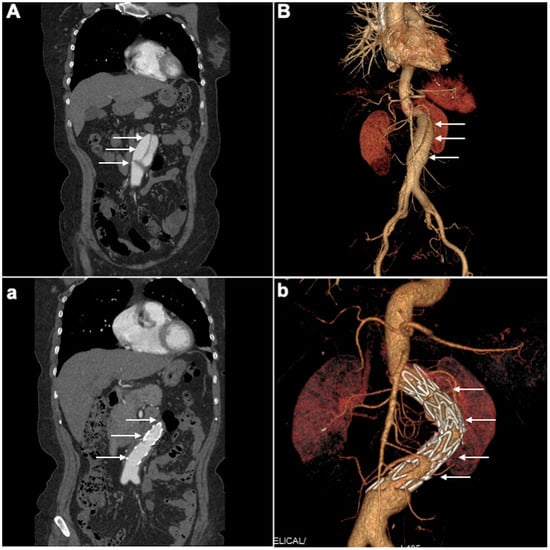

4.2. CTA Imaging Findings